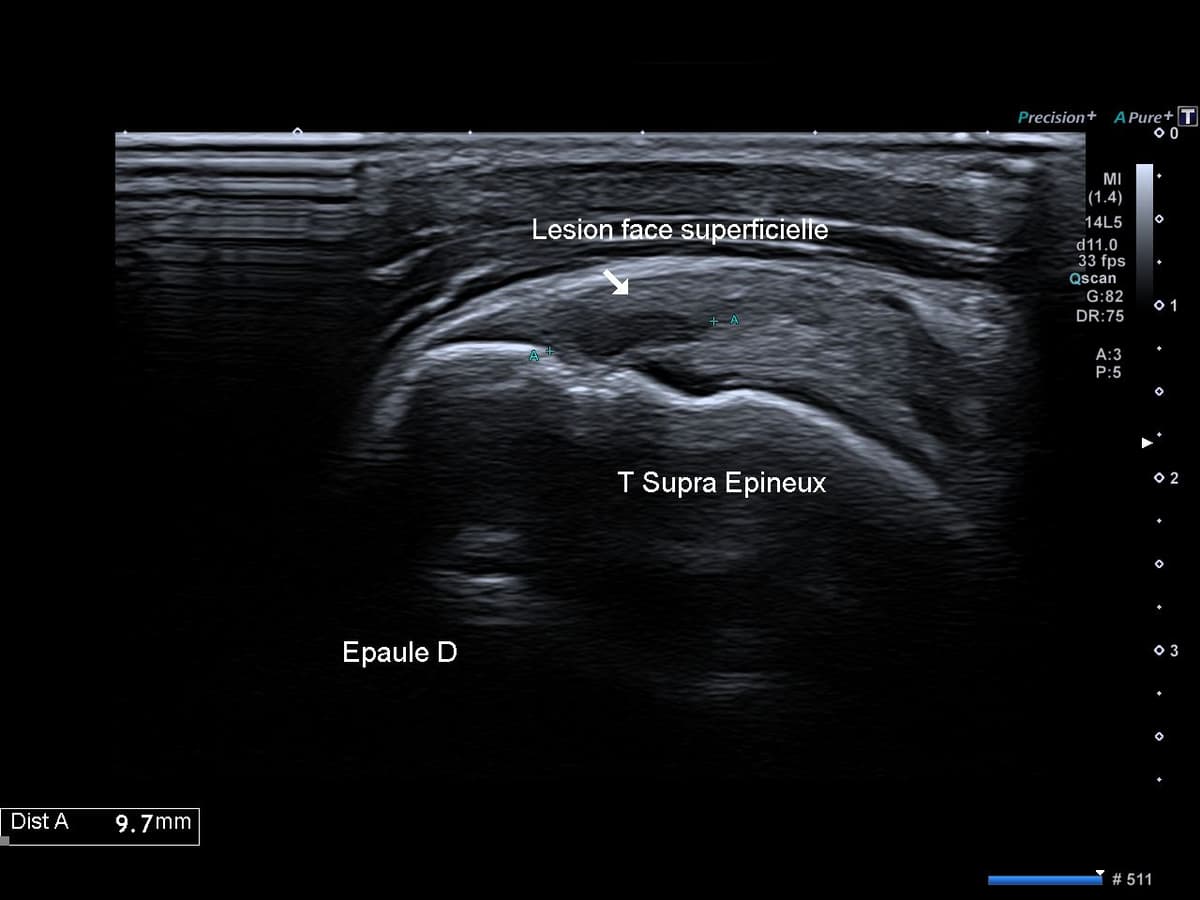

Coiffe des rotateurs ruptures partielles du tendon supra epineux face bursale

Rupture partielle du tendon supra épineux (face bursale)

Scapulalgie droite non traumatique en lien avec une lésion dégénérative partielle de la coiffe des rotateurs.